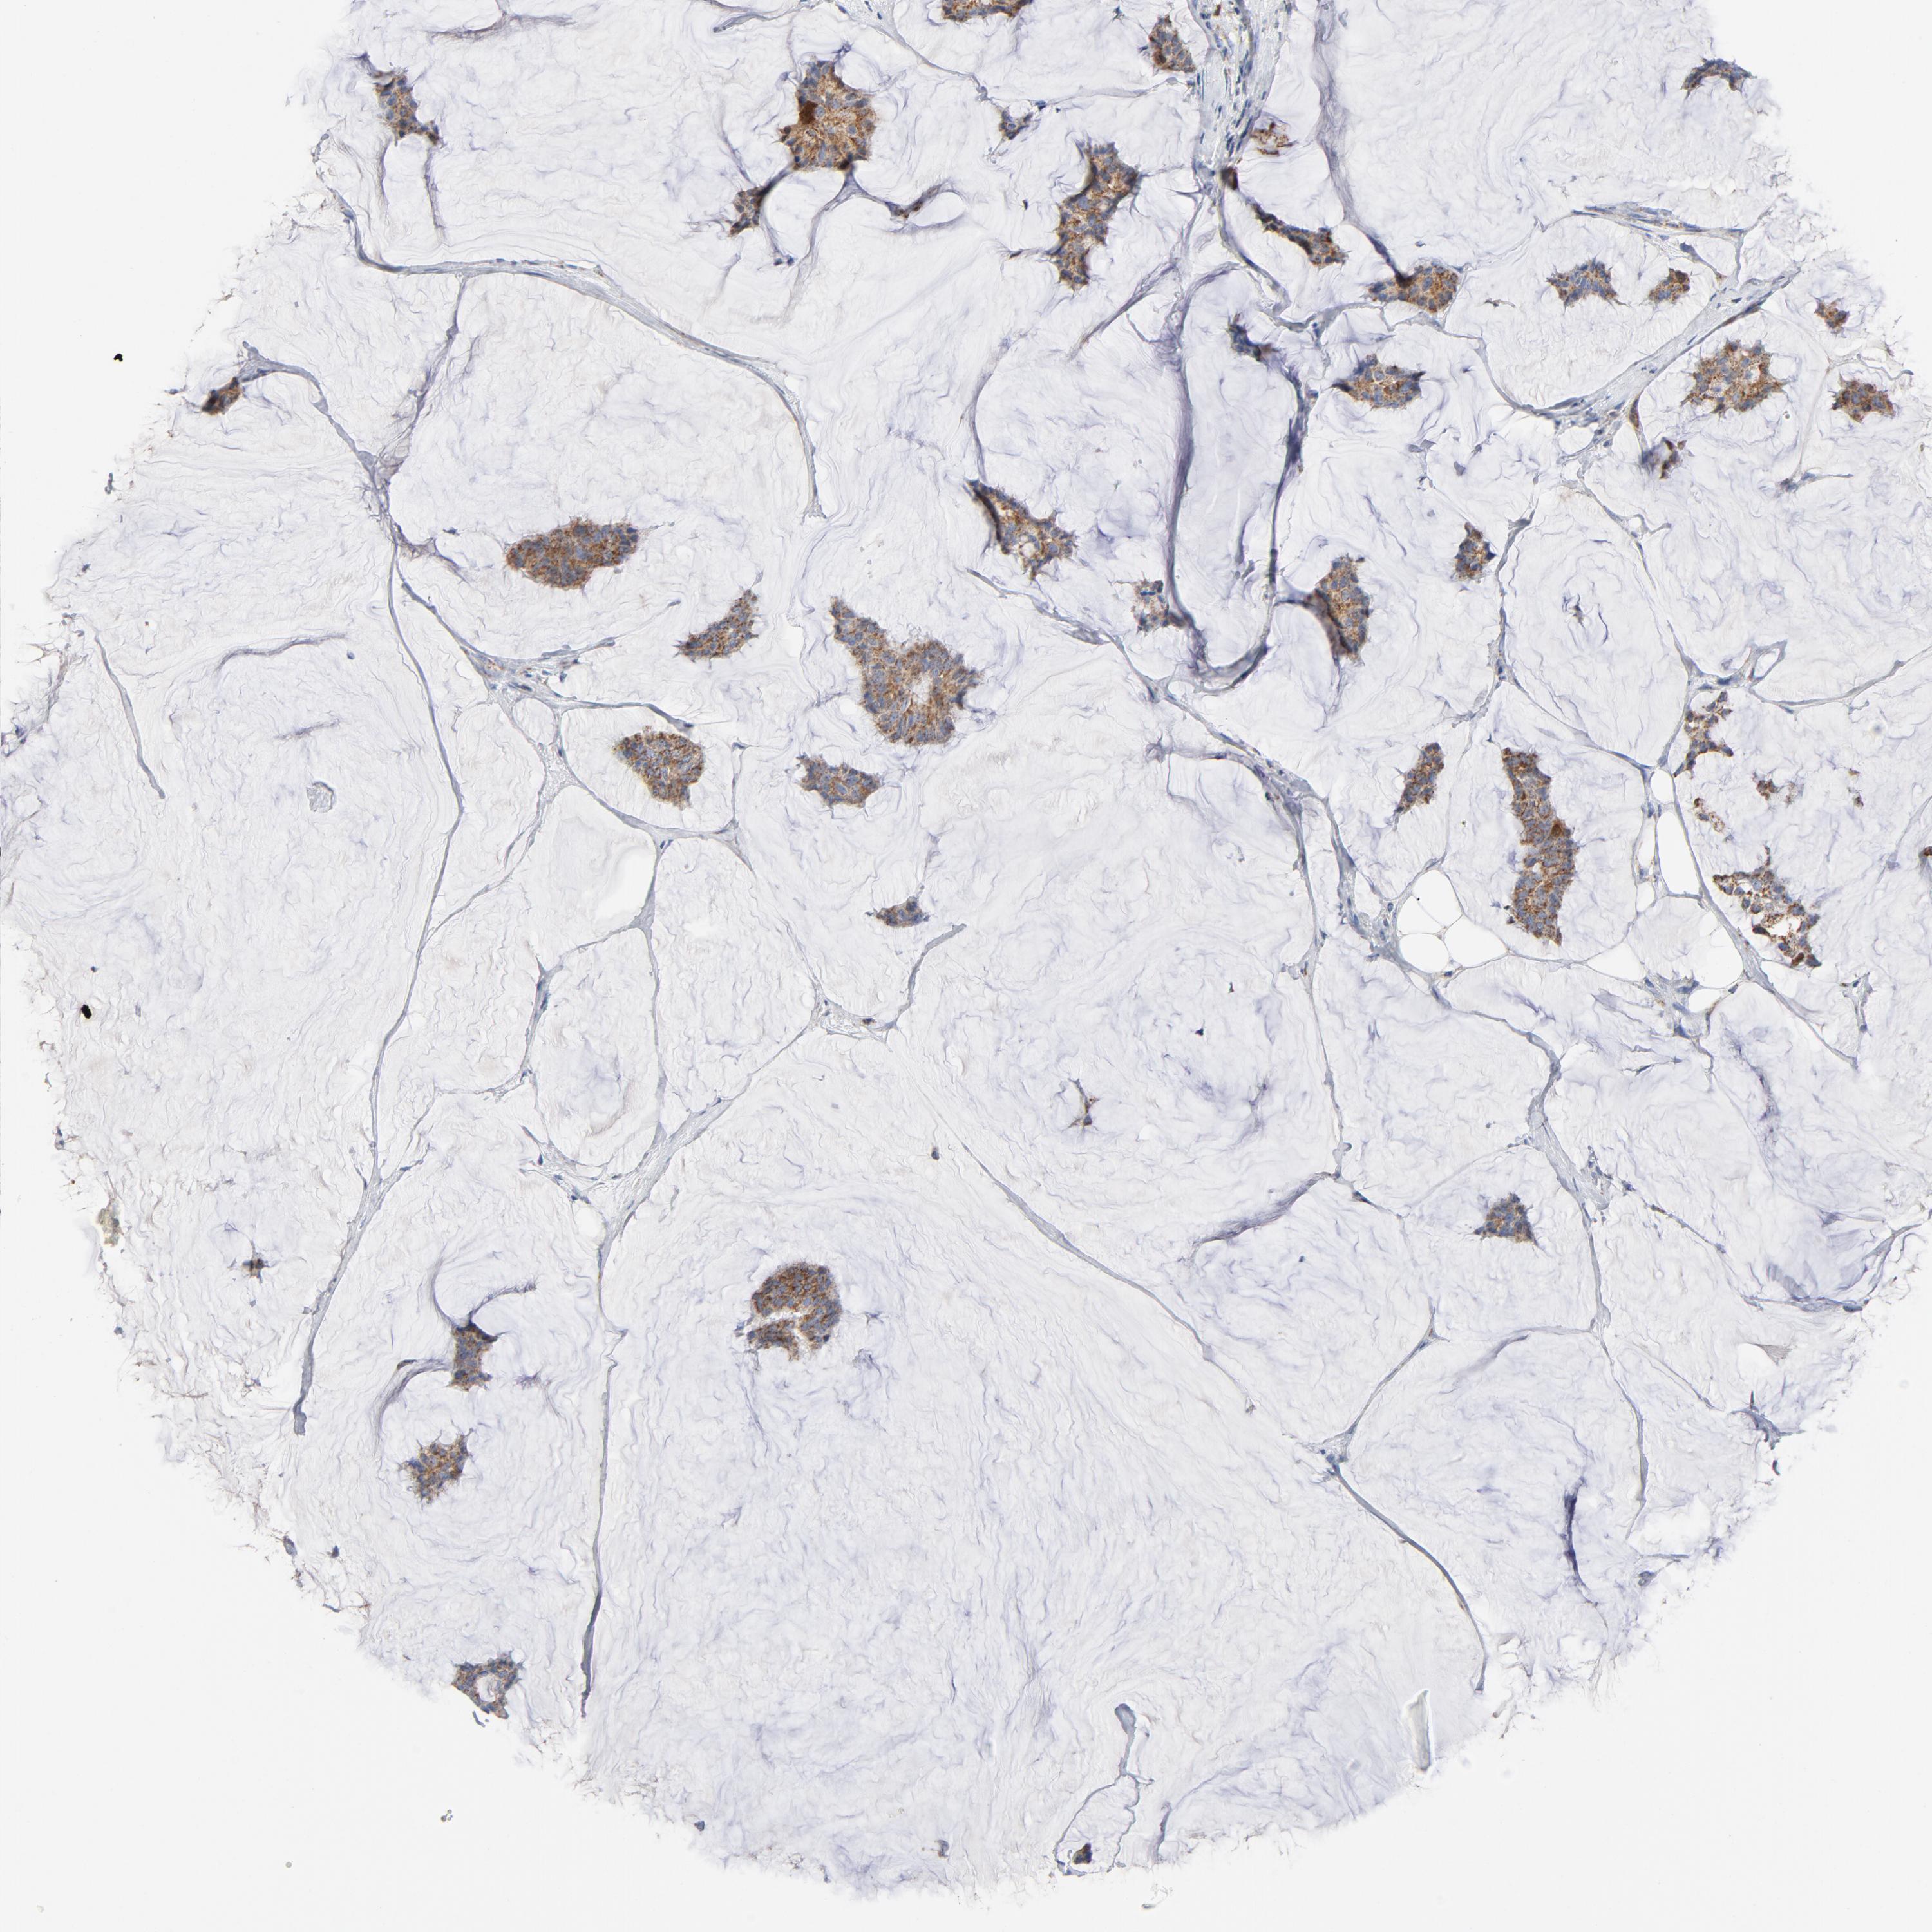

CANCER BREAST CANCER Show tissue menu

BRCA TCGA BRCA VALIDATION PROTEIN EXPRESSION

Breast cancer

Human cancer